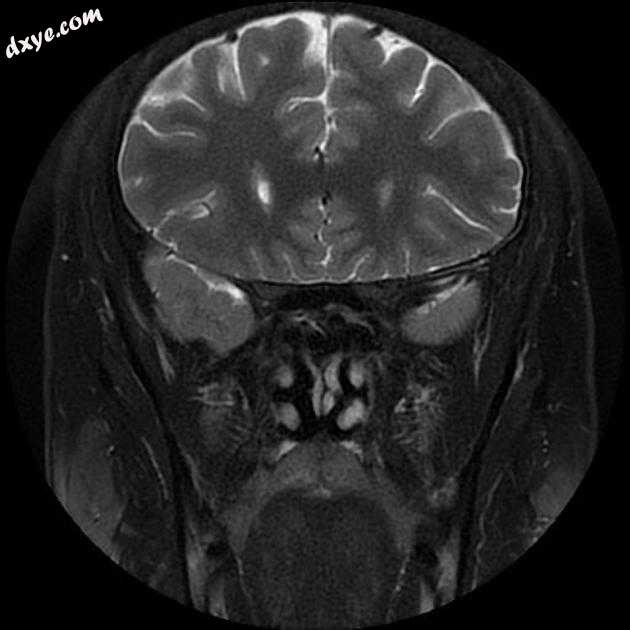

Coronal T2 fat sat

MRI 序列显示右侧颈内动脉的部分血栓囊状动脉瘤位于 C6/7 节段的交界处,大小为 11 x 7 毫米,颈部为 2.5 毫米,压迫动眼神经 (III) 的相邻节段,在 T1 上清晰可见和 FIESTA 序列。

位于 C6/7 交界处的右侧颈内动脉部分血栓囊状动脉瘤的 MRI 特征,压迫同侧动眼神经 (III)。